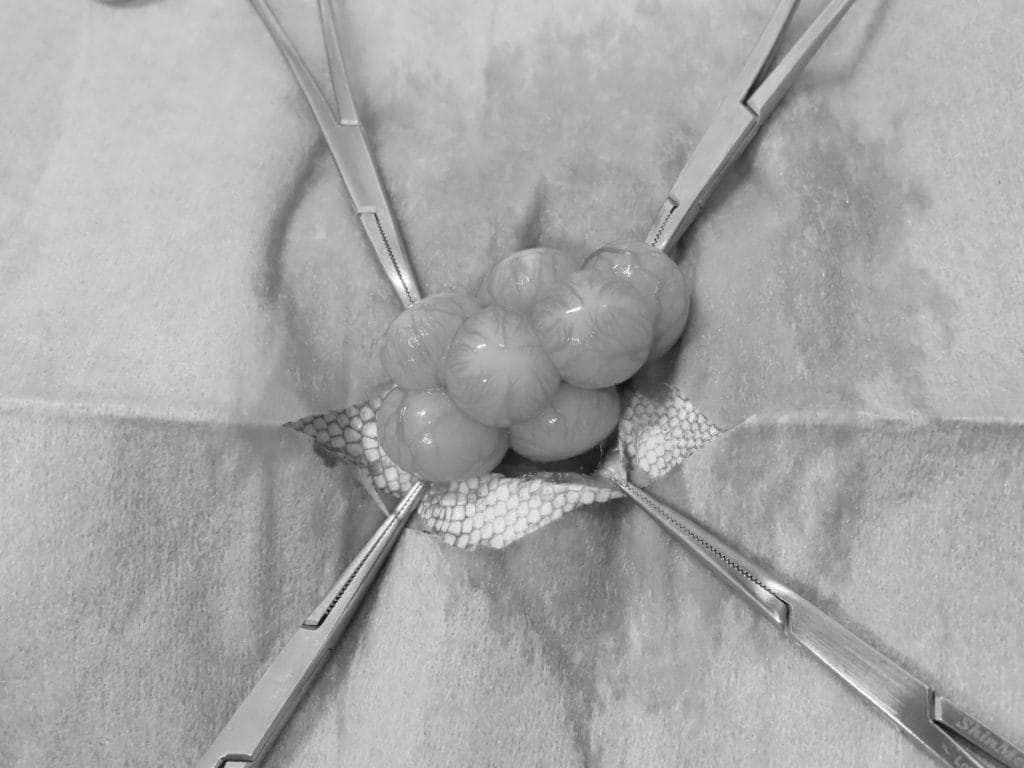

開腹するとこのように多くの卵胞が発達しています。この子は右卵巣で顕著に発達していました。

このように左右の卵巣と卵管です。